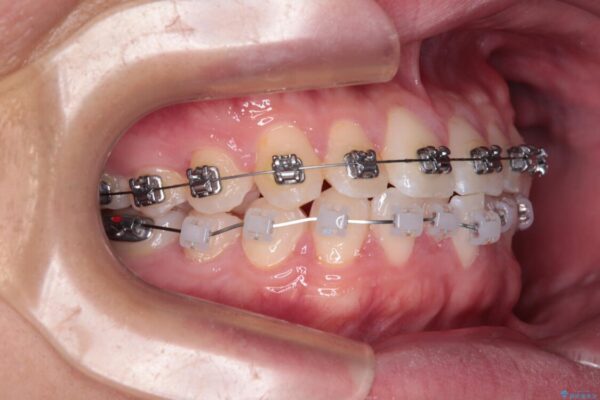

・費用と期間を抑えるために、多少目立っても効率の良いメタルブラケットを使用

・奥歯のシザーズバイト改善には、口蓋側にアンカースクリュー(TAD)を設置し、矯正用ゴムで内側に牽引

・捻転した第二小臼歯は、ワイヤーと矯正用ゴムの力を用いて正しい位置へ回転移動

治療途中

• 前歯のガタガタ・奥歯のかみ合わせ(シザーズバイト)を改善|1年半で完了したメタルブラケット矯正 治療途中画像